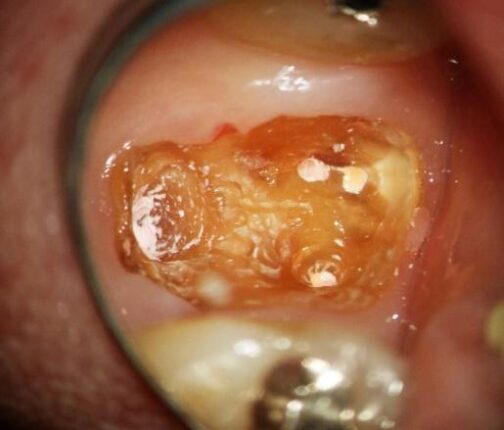

2. 隔壁

「隔壁」とは、治療中の歯に壁を作る処置を指します。

この隔壁を作らないと、次の段階の「ラバーダム」ができません。

隔壁が作れない歯は、根管治療ができない可能性が高くなります。特に奥歯の場合はこのようなケースがあります。

当院の根管治療では、必ず隔壁を作り、仮封剤(仮の蓋)には、光重合型コンポジットレジン(歯と同色の合成樹脂)を使用します。

図1. 歯肉縁上の残存歯質がなく、残根状態

図2. 隔壁を製作して接着した状態